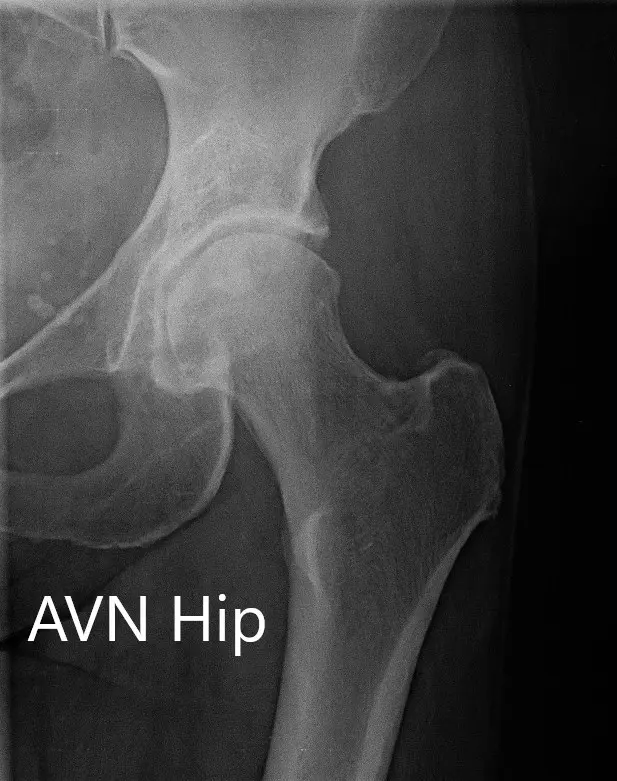

Imaging revealed osteoarthritic changes of the left hip with an AVN lesion that involves 60% of the femoral head. An MRI was obtained which revealed left femoral head avascular necrosis without overt subchondral collapse.

X-ray showing the AP and frog-legged lateral views of the left hip joint